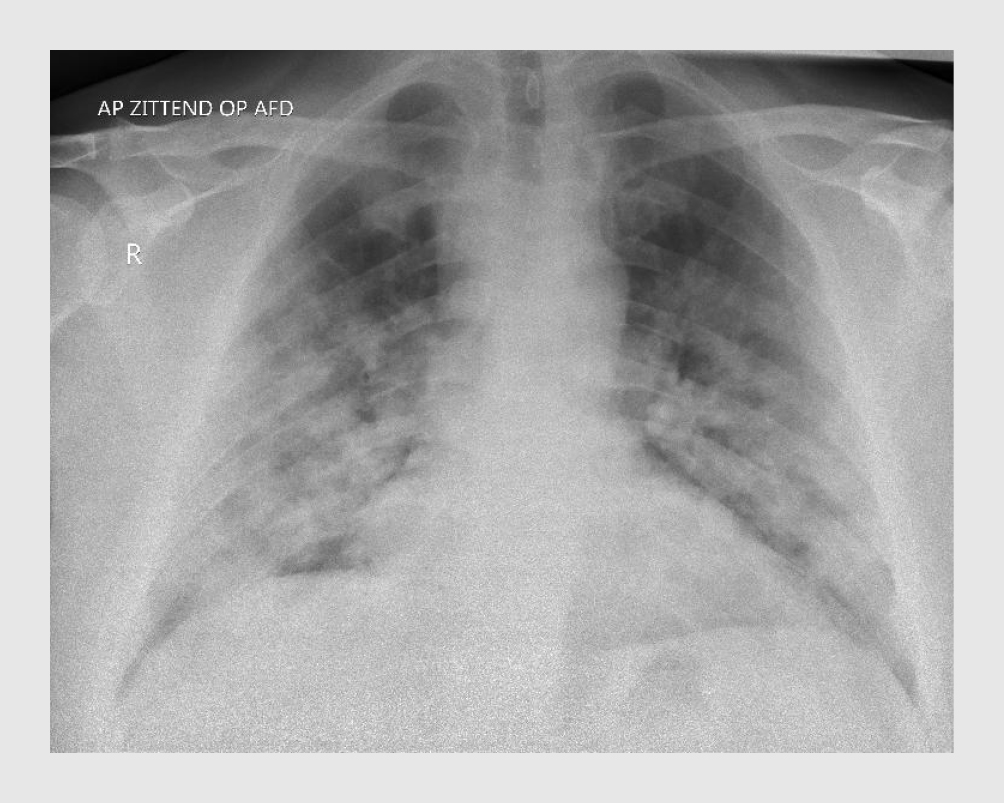

Patiënt heeft op de SEH een lichaamstemperatuur van 38,9°C, de polsfrequentie is 82/min, de bloeddruk 123/72 mmHg en de ademfrequentie 20/min. De perifeer gemeten zuurstofsaturatie (Spo2) zonder toediening van extra O2 is 97%. Hij is goed aanspreekbaar en transpireert in bed. Over de longen zijn niet-afwijkende longgeluiden hoorbaar, zonder bijgeluiden. De thoraxfoto toont beiderzijds vlekkige consolidaties, deels confluerend in de midden- en ondervelden (figuur 1).

Figuur 1

Thoraxfoto van een patiënt met COVID-19

Figuur 1 | Thoraxfoto van een patiënt met COVID-19

Voorachterwaartse opname van de thorax van patiënt A. Beiderzijds zijn vlekkige consolidaties te zien, deels confluerend in de midden- en ondervelden.